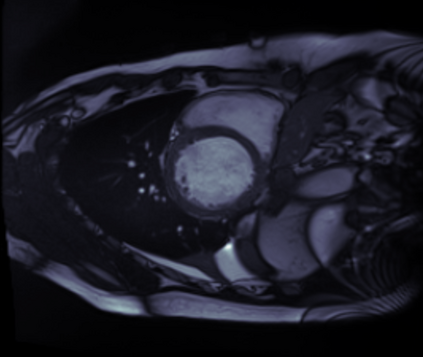

Supervised machine learning provides state-of-the-art solutions to a wide range of computer vision problems. However, the need for copious labelled training data limits the capabilities of these algorithms in scenarios where such input is scarce or expensive. Self-supervised learning offers a way to lower the need for manually annotated data by pretraining models for a specific domain on unlabelled data. In this approach, labelled data are solely required to fine-tune models for downstream tasks. Medical image segmentation is a field where labelling data requires expert knowledge and collecting large labelled datasets is challenging; therefore, self-supervised learning algorithms promise substantial improvements in this field. Despite this, self-supervised learning algorithms are used rarely to pretrain medical image segmentation networks. In this paper, we elaborate and analyse the effectiveness of supervised and self-supervised pretraining approaches on downstream medical image segmentation, focusing on convergence and data efficiency. We find that self-supervised pretraining on natural images and target-domain-specific images leads to the fastest and most stable downstream convergence. In our experiments on the ACDC cardiac segmentation dataset, this pretraining approach achieves 4-5 times faster fine-tuning convergence compared to an ImageNet pretrained model. We also show that this approach requires less than five epochs of pretraining on domain-specific data to achieve such improvement in the downstream convergence time. Finally, we find that, in low-data scenarios, supervised ImageNet pretraining achieves the best accuracy, requiring less than 100 annotated samples to realise close to minimal error.